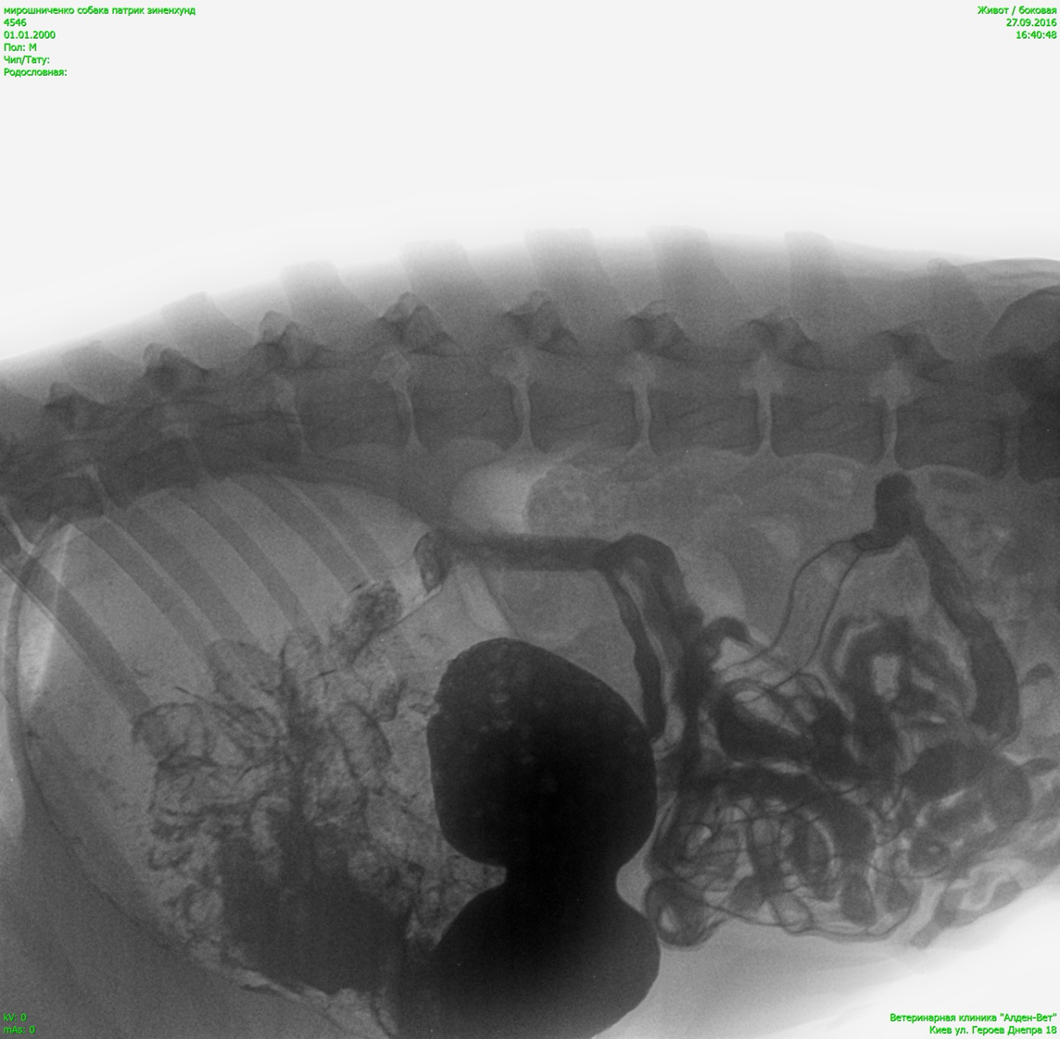

Оберіть рентгенівське зображення відповідно діагнозу.

View this question

Яка викладка (проекція) зображена на знімку:

рентген